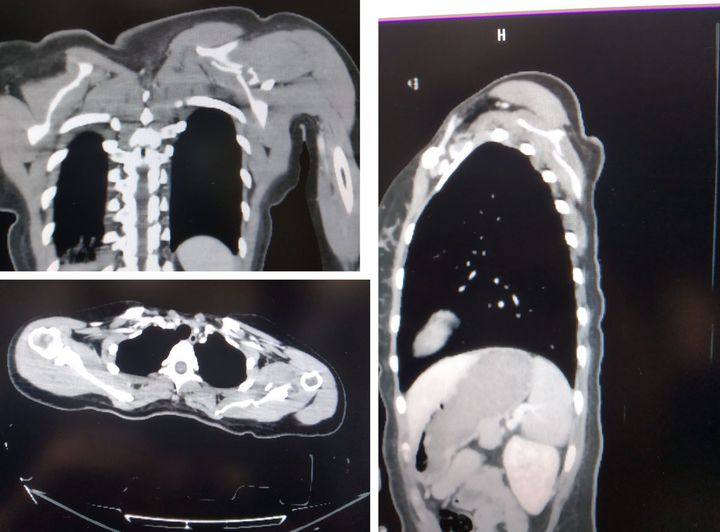

24 years old female patients.Left scapula fracture due to accident